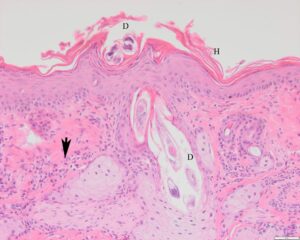

| Ree met demodicose | Microscopisch beeld van de huid bij demodicose. D = demodex-mijt, H = hyperkeratose, Pijl = ontsteking |

De demodex-mijt leeft in de haarzakjes en komt zeer algemeen voor bij dieren. Normaal gesproken veroorzaakt ook de demodex-mijt geen problemen voor een dier, maar als het door één of andere reden verzwakt is, kunnen de aantallen mijten toenemen en kunnen ontstekingen ontstaan waardoor het dier zijn haren verliest. De ontstekingen in en rond de haarfollikels zijn alleen met microscopisch onderzoek van de huid vast te stellen. Bij kaalheid door de demodex-mijt wordt ook wel gesproken van demodicose.

In extreme gevallen worden de reeën bijna geheel kaal. Van de 51 reeën met kale plekken die bij het DWHC zijn onderzocht, is de demodex-mijt bij 5 dieren gevonden en als oorzaak aangemerkt voor de kaalheid. e mijt loopt over de huid van het ene haarzakje naar het volgende en kan dan bij intensief onderling contact tussen reeën overgaan van het ene dier op het andere. Zie voor meer voor meer informatie over demodicose het DWHC-bericht ‘Kale reeën door demodex-mijten’.